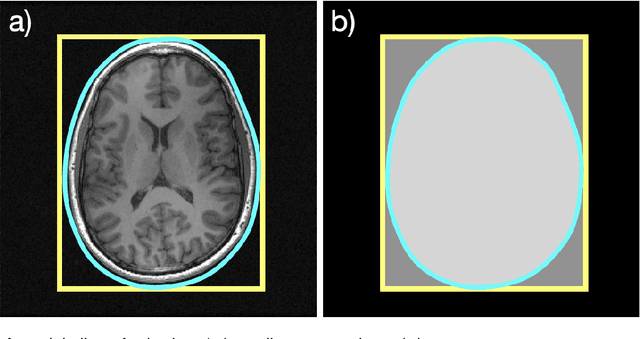

Abstract:With Fourier sensing, it is commonly the case that the field-of-view (FOV), the area of space to be imaged, is known prior to reconstruction. To date, reconstruction algorithms have focused on FOVs with simple geometries: a rectangle or a hexagon. This yields sampling patterns that are more burdensome than necessary. Due to the reduced area of imaging possible with an arbitrary (e.g., non-rectangular) FOV, the number of samples required for a high-quality images is reduced. However, when an arbitrary FOV has been considered, the reconstruction algorithm is computationally expensive. In this manuscript, we present a method to reduce the sampling pattern for an arbitrary FOV with an accompanying direct (non-iterative) reconstruction algorithm. We also present a method to decrease the computational cost of the (iterative) model-based reconstruction (MBR) algorithm. We present results using MRI data of an ankle, a pineapple, and a brain.